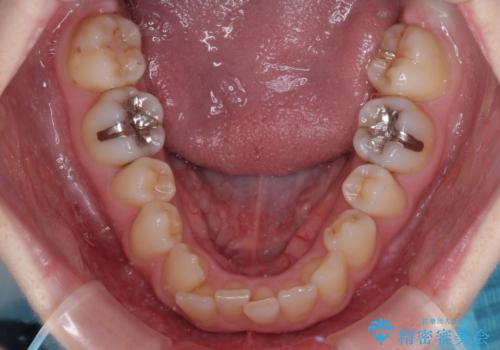

- 前歯のデコボコをクロスバイトを気にして来院された患者様です。

上顎骨の横幅が狭く、上下ともに内側に倒れ込んだ混み合った歯列となっていました。

左右ともに奥歯の咬み合わせには大きな問題がなく、窮屈な歯列を解決すれば歯列を整えることできたため、僅か1年で終えることができました。